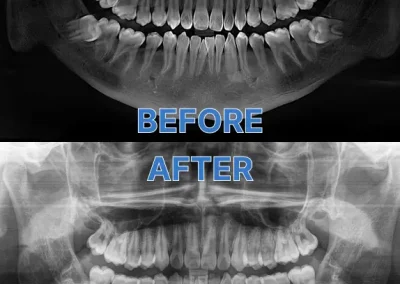

Extractions Case 1 Good Choice Dental

Full wisdom teeth extraction